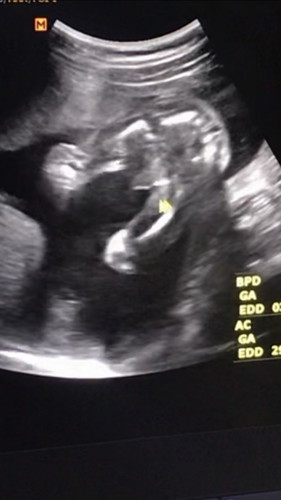

หมอบอกว่าผู้ชายค่ะ แต่ที่สงสัยคือรูปแรกเห็นเป็นจู๋ชัดแจ๋วเลยแต่พอมาดูรูป2รู้สึกแปลกๆค่ะ55555 จู๋น้องมันขาดหายไปไหนหรืออาจจะเป็นเพราะแสงเงาก็ยังไม่แน่ใจค่ะ มีแม่ๆคนไหนที่หมอบอกว่าเป็นผู้ชายแต่ออกมาเป็นผู้หญิงไหมคะ#ขอบคุณสำหรับคำตอบค่ะ